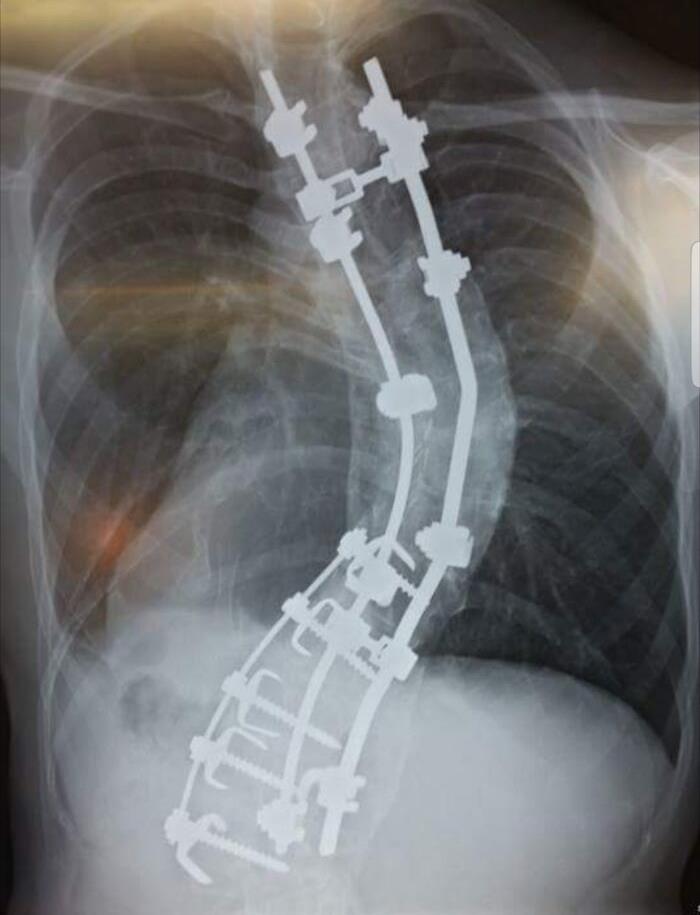

My Spine. I Went In For Surgery At 5'10", Came Out 6'2", I'm Supposed To Be 6'7"